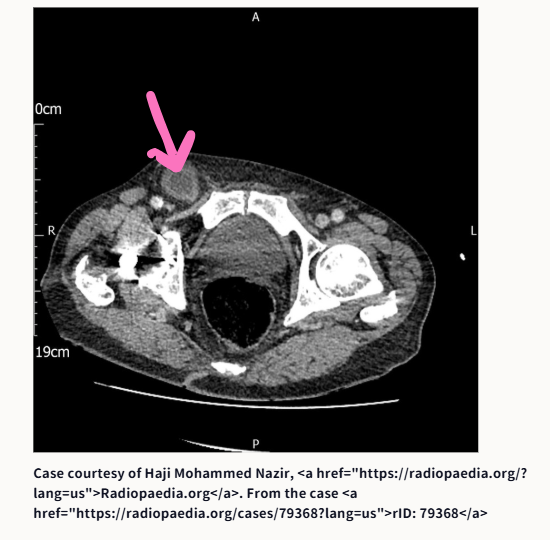

③腸閉塞です。原因は何でしょうか?

③腸閉塞の原因は、鼠径ヘルニア嵌頓です

こあら先生が提示したCT画像は、以下のサイトからのものです。ピンクの矢印は、こあら先生が書き込んだものです。